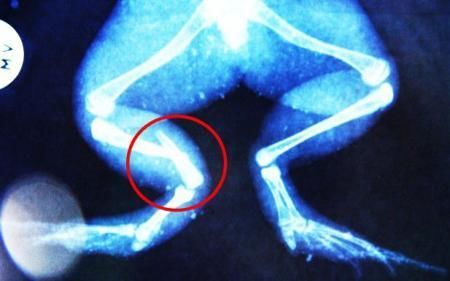

環(huán)球網(wǎng)4月2日報(bào)道 據(jù)《每日郵報(bào)》報(bào)道,上個(gè)月,南非大牛蛙布魯萊的右小腿被鄰居家的一只狗咬到,導(dǎo)致粉碎性骨折,現(xiàn)在經(jīng)過2個(gè)小時(shí)的手術(shù),它的斷腿已經(jīng)被接上,它也因此成為有史以來第一只通過外科手術(shù)用鋼針接上斷腿的青蛙。

布魯萊的主人,居住在南非約翰內(nèi)斯堡附近的62歲的安妮·米恩斯說:“我對這只青蛙如此關(guān)心,人們一定認(rèn)為我瘋了,但是我無法眼睜睜看著它那么痛苦。青蛙因其靈活的腿腳而著稱,一想到布魯萊的腿里要留下一個(gè)薄金屬片,我就感到心痛。然而我知道,如果不進(jìn)行手術(shù),布魯萊以后就沒辦法動(dòng)彈了。因此我匆匆趕到獸醫(yī)那里,央求他給這只可憐的青蛙動(dòng)手術(shù)。這位獸醫(yī)整天救助小貓小狗,他很難理解為什么我這么擔(dān)心一只青蛙,但是最終他還是答應(yīng)了給布魯萊做手術(shù)。手術(shù)后是幾個(gè)小時(shí)的焦急等待,我們希望它能快快蘇醒過來。不過現(xiàn)在它的傷口已經(jīng)愈合,又能在花園里跳來跳去了。X光照射顯示,它會(huì)恢復(fù)的跟以前一樣。”

野生生物專家安妮經(jīng)常為學(xué)校寫教材,她認(rèn)為這是人類第一次通過手術(shù)給一只青蛙接斷腿。在手術(shù)開始階段,獸醫(yī)把少量給狗用的麻醉藥注入到這只青蛙體內(nèi),讓它失去知覺。然后他在布魯萊的斷腿上切開一個(gè)小口,把一根小鋼針植入腿里。最后獸醫(yī)給它縫了9針,把切口縫合在一起。僅僅幾周后,布魯萊就能在安妮家附近活動(dòng)了。這只青蛙大約已有25歲,主要以嚙齒動(dòng)物、蛇和其他青蛙為食。布魯萊所屬的牛蛙種群正在不斷減小,目前只能在非洲南部的濕地里才能看到這種青蛙。